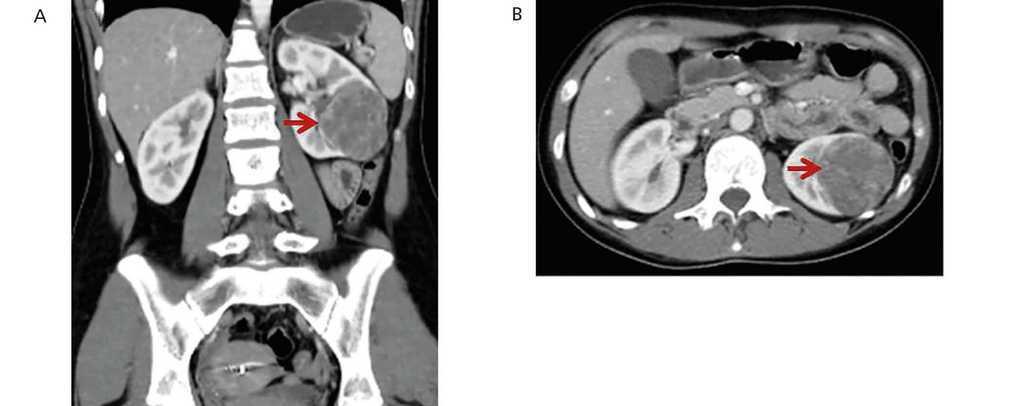

Two years later, on medication with enalapril, losartan and amlodipine, she was admitted to the emergency department of our hospital due to occipital neuralgia and muscle weakness lasting several days. She had BP of 220/140mmHg. In the initial studies, hypokalaemia of 2mEq/l, plasma creatinine of 0.6mg/dl and plasma urea of 25mg/dl were detected. The renal ultrasound displayed the image of a solid nodule, confirmed by abdominal computerised tomography with contrast, in which a solid, voluminous, hypervascular, space-occupying formation of 65mm in diameter was observed in the interpolar and lower pole sector of the left kidney (Figure 1). The ultrasound and Doppler ultrasound of renal arteries did not show abnormalities.

Figure 1. CT images of the left renal tumour (arrows)